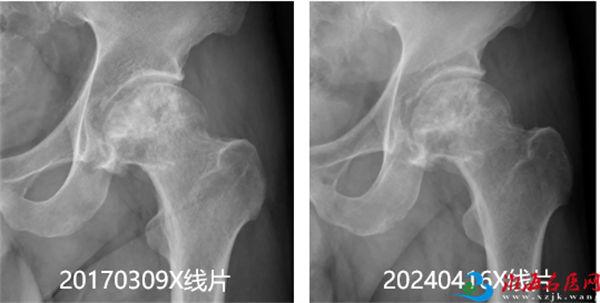

康复出院后,王先生前往苏州发展,并创立了自己的公司,左股骨头也再没有出现任何不适。今年4月,王先生突然想起自己左股骨头坏死介入治疗后已7年余,主动联系徐州市中医院介入科进行复查。经摄X线片、MR及CT检查,评估病情为左股骨头坏死Ⅱ期病变,股骨头原坏死区明显减小,骨质修复明显;骨髓无肿胀,关节腔无明显积液;右股骨头无异常。